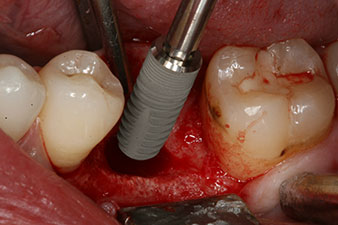

Implantat

Fig. 3: After preparation with the Implantmed implantology motor, an implant (diameter 4 mm, length 12 mm) was screwed in by the motor at a torque of 43 Ncm.

The implant was placed as planned after thorough removal of the granulation tissue (blueSky, bredent).

The torque used for the machine-driven placement was 43 Ncm. In addition, after screwing a measuring post (SmartPeg) specially matched to the implant, the ISQ value was measured with the probe of the W&H Osstell ISQ module.